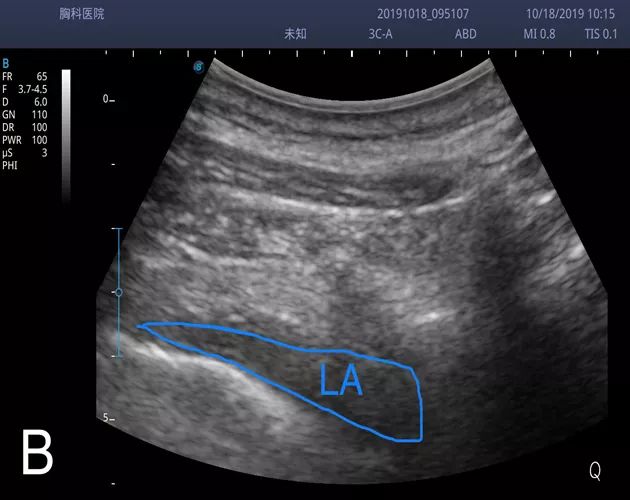

(A、B分别为注药前后椎旁间隙影像。图B见胸膜下移,所示液性暗区为局麻药液。)